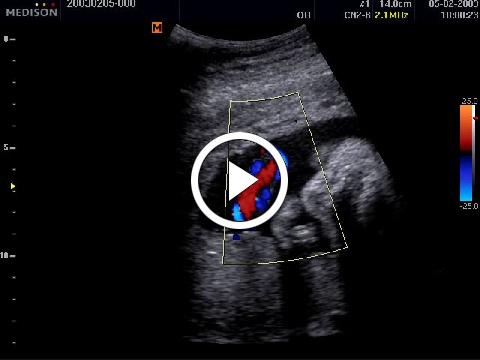

2. Color-mód Cine képei